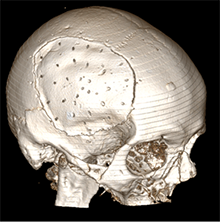

6 pav. Perforacijos KPL

Dėl anksčiau gydytų EDS, susidariusių atlikus KP, klinikinėje praktikoje KPL buvo atlikta daugybinių perforacijų. Mokslinės literatūros duomenimis, KPL, turinčio fenestracijų, daug geresnės išeitys negu KPL, neturinčio fenestracijų [11], nes EPS susisiekia su subgaliniu tarpu ir dėl slėgių gradiento rezorbuojasi į minkštuosius audinius. Per padarytas skylutes EDS susisiekia su subgaliniu tarpu, seroma labiau kaupiasi po minkštaisiais audiniais negu epiduraliai. Nustatyta, kad aponeurozei būdinga gera rezorbcija, todėl EDS linkusios regresuoti [12].

Straipsnyje aptariamu atveju paciento KPL skirtinas mažiausiai (75 cm2) grupei, kuriai būdinga minimali infekcijos atsiradimo rizika (13 pav.), tačiau operacijos metu vis tiek buvo paimtas mikrobiologinis pasėlis infekcijai ekskliuduoti. Mokslinėje literatūroje taip pat pristatomas siekis tirti skirtingų pirminių galvos smegenų hematomų, po kurių reikėjo atlikti kraniektomiją, koreliaciją su EDS, tačiau reikšmingų rezultatų negauta [8].

13 pav. Kranioplastikos lopo dydis (iki 75 cm2)